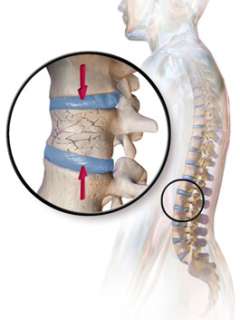

Bone Health Will Improve

Improvements in bone mineral density following parathyroid surgery are very well established, and patients can routinely expect these benefits soon after surgery. Bone mineral density will significantly increase in the year following surgery, and continue to increase over the next 10 years.

What is Osteoporosis?

Osteoporosis is a weakening of your bones, which increases the risk of a fracture. People with osteoporosis have bones that break too easily (for example, after a fall on the sidewalk).

How Does Hyperparathyroidism Cause Osteoporosis?

Answer: Hyperparathyroidism causes one or more of the parathyroid glands to produce too much parathyroid hormone (PTH). PTH increases bone turnover, and too much PTH causes cortical bone thinning especially in the femoral neck (thigh) and distal radius (forearm).